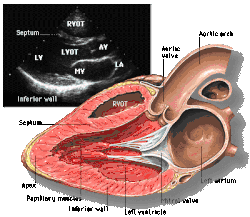

Parasternal long axis

Each figure contains a TTE with a black background, and a corresponding colored illustration. Patrick J. Lynch and C. Carl Jaffe, Yale University, 2006.

Click on a figure to enlarge it and see some parts of the heart identified. RV, right ventricle; LV, left ventricle; RA, right atrium; LA, left atrium; TV, tricuspid valve; MV, mitral valve; AV, aortic valve; RVOT, right ventricular outflow tract; LVOT, left ventricular outflow tract